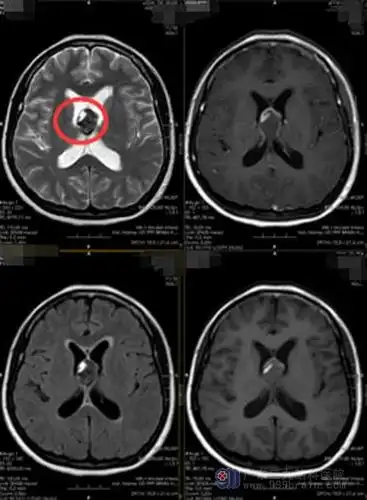

眩晕课堂757讲——脑干出血致命的"不定时炸弹"海绵状血管瘤